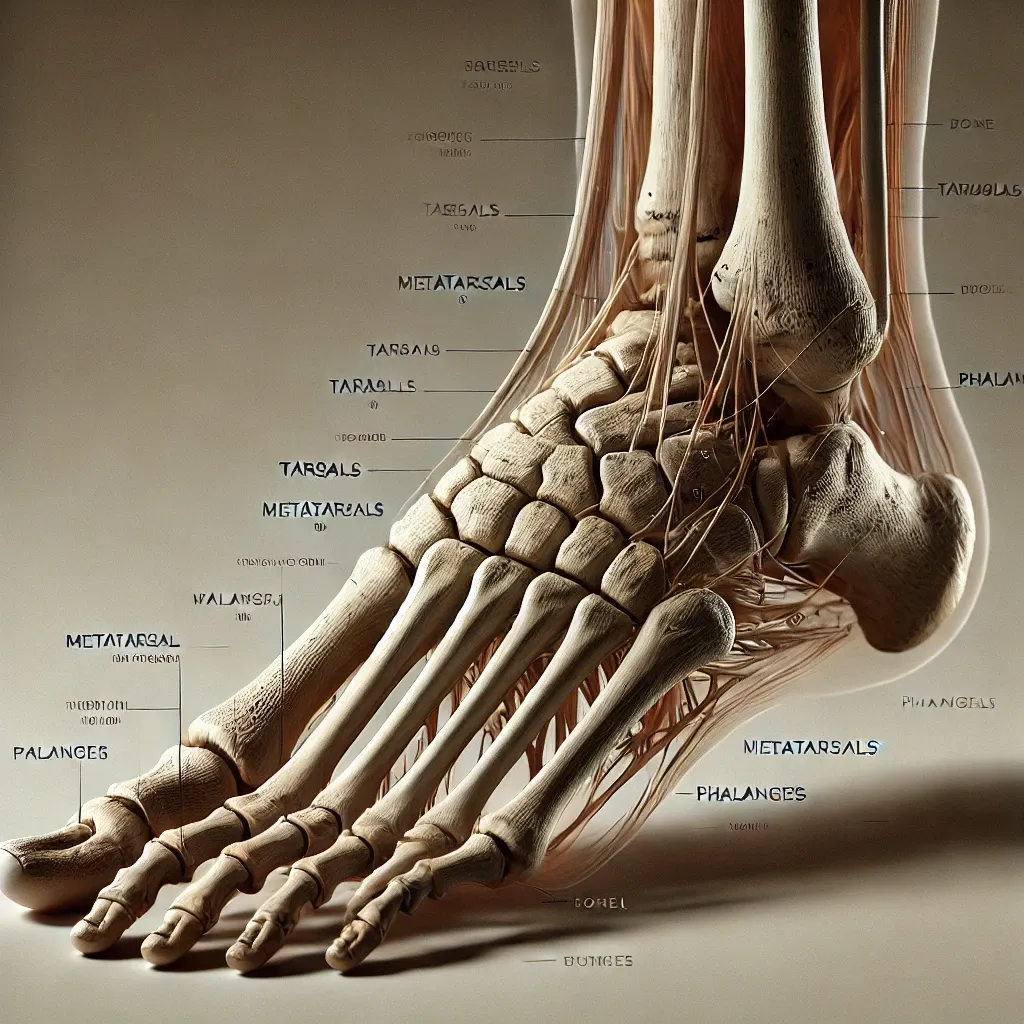

📋 목차아킬레스건염의 주요 원인아킬레스건염의 증상아킬레스건염의 진단 방법아킬레스건염의 치료법효과적인 스트레칭 방법아킬레스건염 예방 방법생활습관 개선 팁아킬레스건염 관련 자주 묻는 질문 FAQ아킬레스건염은 아킬레스건의 과도한 사용이나 부상으로 인해 발생하는 질환입니다. 반복적인 움직임, 부적절한 자세, 혹은 적절한 관리 부족으로 인해 쉽게 나타날 수 있습니다. 이를 효과적으로 관리하기 위해 증상의 원인을 파악하고 적절한 스트레칭과 생활습관 개선을 병행하는 것이 중요합니다. 아킬레스건염의 주요 원인아킬레스건염은 여러 요인으로 인해 발생할 수 있습니다. 반복적인 운동이나 과도한 훈련은 아킬레스건에 부담을 주어 염증을 유발할 수 있습니다. 특히 달리기나 점프 같은 고강도 운동이 큰 영향을 미칩니다. 또한, 평..